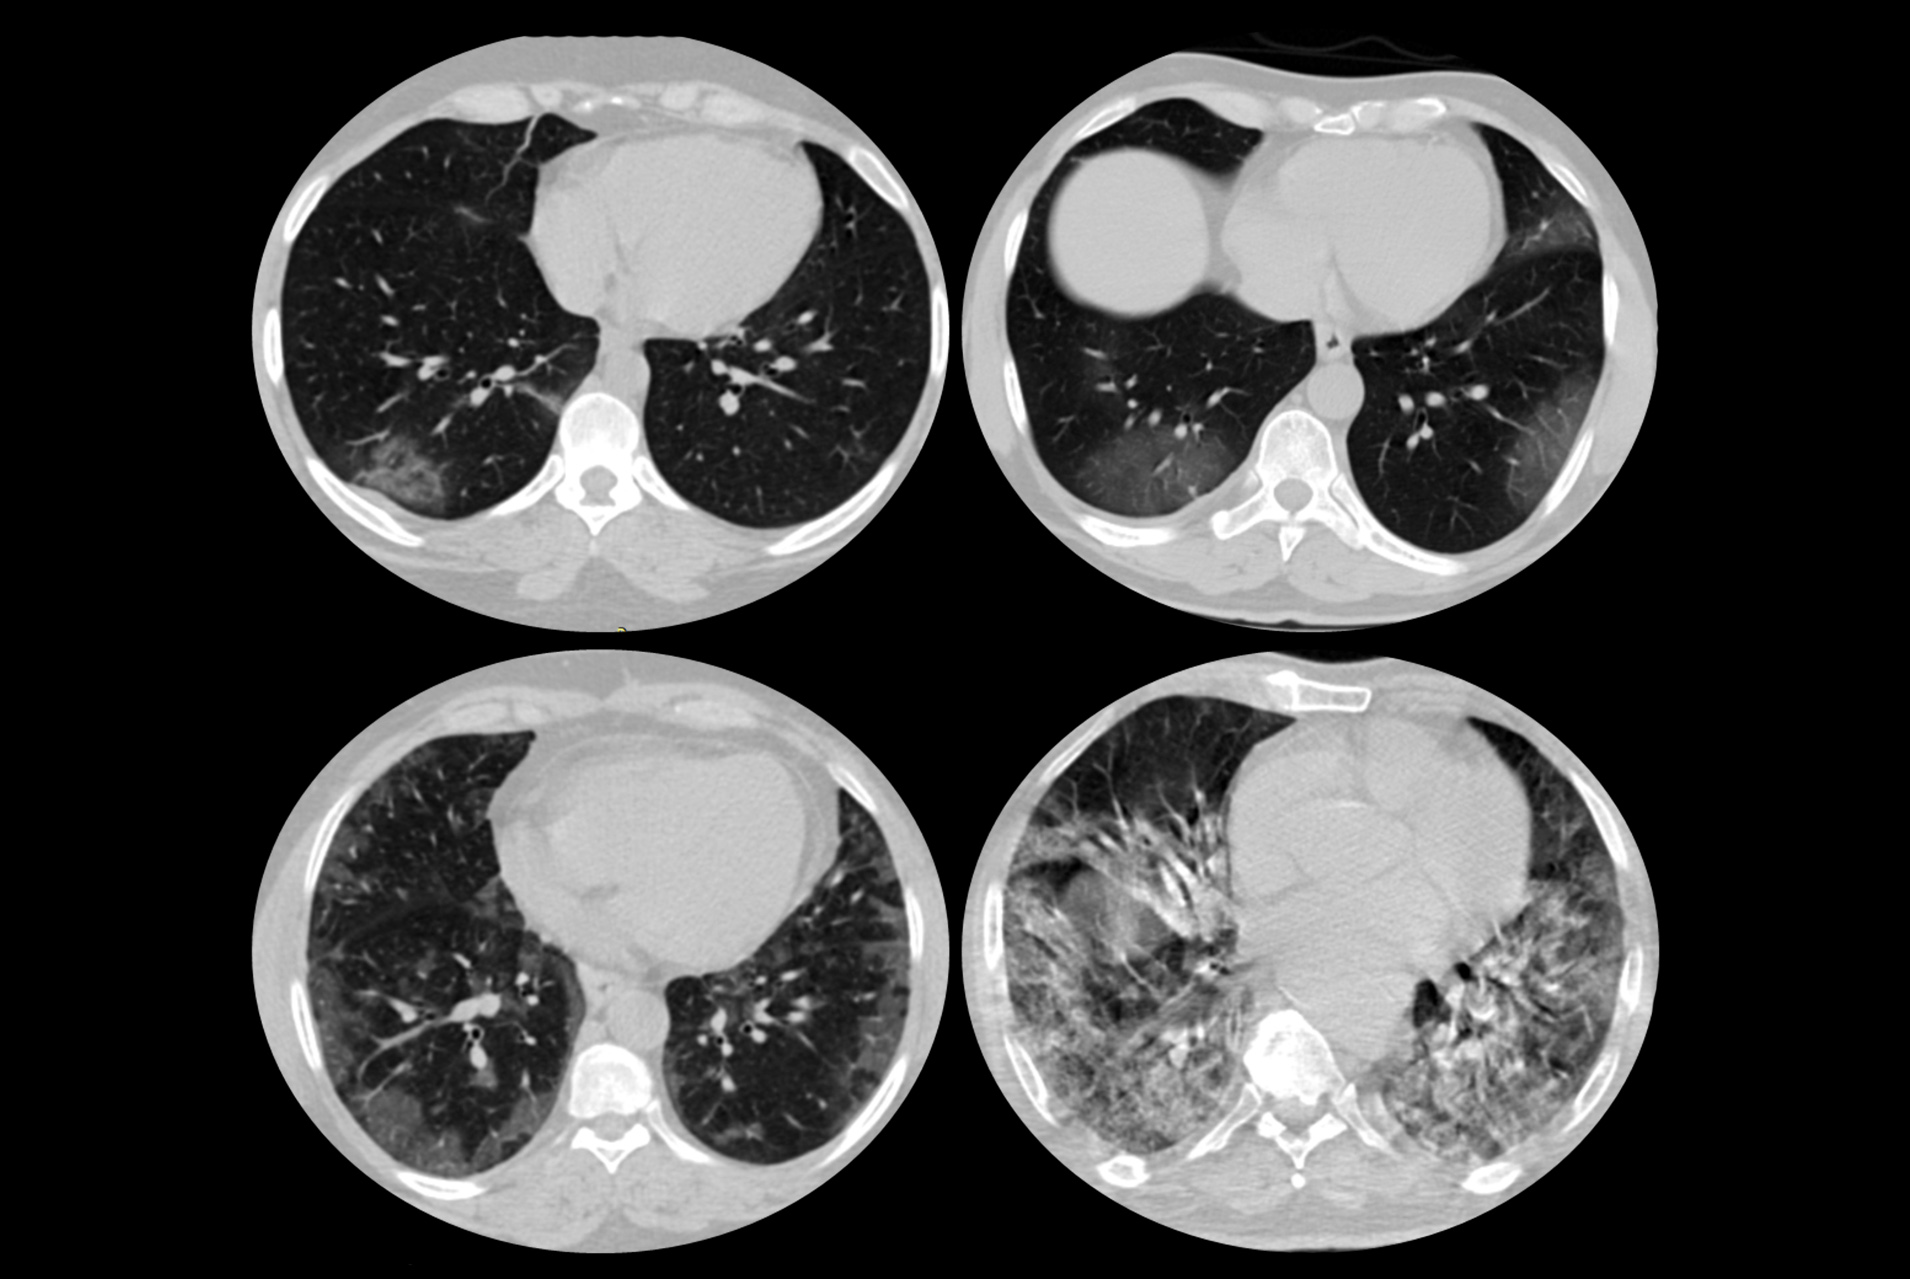

Chest computer tomography (CT) is being used extensively in patients with known and suspected COVID-19 infection, especially when there is limited availability of conventional testing with nasal or oral swab (PCR). Some patients may need to undergo multiple chest CT scans as part of their medical examination.

In this webinar, radiology experts will present best practices for chest CT including scan parameters and related radiation doses with specific emphasis on COVID-19 imaging with CT. Using generic examples, they will discuss how best to serve patients with appropriate and optimal use of radiology resources and expertise.

1. To learn about principles of protocol and dose optimization for chest CT

2. To understand issues with chest CT in COVID-19 infection